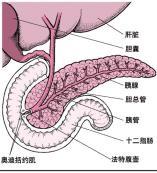

环形胰腺

628健康网为您分享有关环形胰腺的症状,环形胰腺的治疗方法,环形胰腺的预防知识,环形胰腺的症状图片,环形胰腺吃什么药,环...